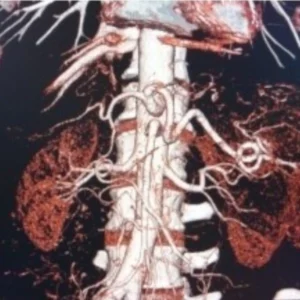

Vascular Anomalies of the Kidney

Crossing vessel at PUJ

Vascular malformations of the kidney are disease processes that involve renal veins and arteries and include congenital arteriovenous malformations (AVMs) and arteriovenous fistulas. AVMs are congenital communications between arteries and veins with a vascular nidus that bypass the capillary bed.

Renal hilar vessels

The renal hilum (Latin: hilum renale) or renal pedicle is the hilum of the kidney, that is, its recessed central fissure where its vessels, nerves and ureter pass. The medial border of the kidney is concave in the center and convex toward either extremity; it is directed forward and a little downward.